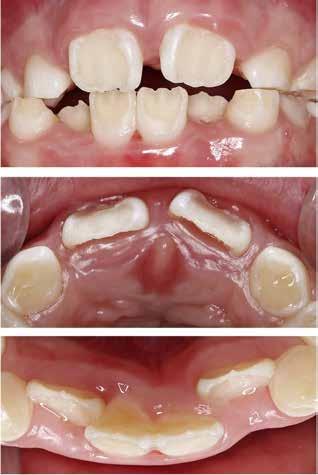

Klinisk undersøgelse viste emaljehypoplasier og hypomineralisering på 1+, +1, 2-, 1-, -1 og -2 (Fig.1). Hun havde Angle klasse II, pladsmangel i begge kæber og agenesi af -5. Der var isninger ved spisning og tandbørstning. Fundene var forenelige

BAGGRUND – Denne kasuistik beskriver en patient, hvor der blev valgt protetisk behandling i ung alder.

PATIENTTILFÆLDE – En niårig pige havde stort behandlingsbehov og smerter fra tænderne på grund af tandudviklingsforstyrrelse. Der var flere gange forsøgt restaurering med komposit, som ikke fungerede. Laminater i feldspatkeram blev valgt for at fjerne mindst mulig tandsubstans, øge holdbarheden på restaureringerne og forbedre æstetikken. Patientens motivation, meninger og kooperationsevne var vigtige for behandlingsvalget, da behandlingen var tidkrævende og til tider udmattende for en ung patient.

KONKLUSION – Resultatet var vellykket og medførte forbedret livskvalitet. Protetisk behandling med adhæsiv teknik kan være et godt behandlingsalternativ for børn og unge på ret indikation.

EMNEORD Adhesives | amelogenesis imperfecta | ceramics | pediatric dentistry | quality of life

Protetisk behandling med adhæsiv teknik –et alternativ i ung alder?